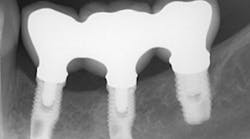

The same arguments have been advanced for not splinting adjacent implants in segmental reconstructions (figure 1). Plaque-related peri-implantitis is the most common biological complication in implant dentistry. A passive fit of prostheses on their supporting implants is considered essential for minimizing mechanical and biological overloading. On the other hand, it is also claimed that splinting can prevent overloading (figure 2). Screw loosening and fracture of veneering material are the most common mechanical complications of loading, although there is little evidence that it results in loss of integration.

Figure 1: Nonsplinted adjacent implants